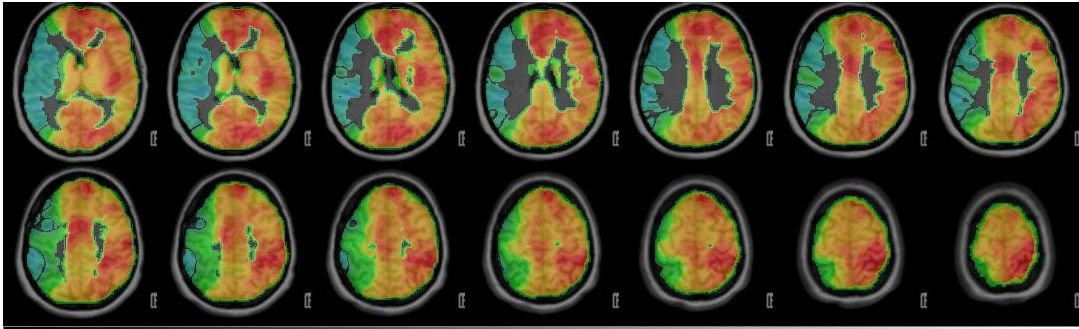

Wissenschaftliche Abbildung

PET/CT mit Darstellung der einseitig reduzierten Reservekapazität/Durchblutung (kalte Farben) im Vergleich zum physiologischen Anstieg der Perfusion auf der Gegenseite (warme Farben).

Die wichtigste Untersuchung zur absoluten Darstellung des Blutflusses im Gehirn im Ruhezustand (baseline) und nach medikamentös stimulierter Gefäßweitstellung ("Diamox/Acetazolamid-Challenge") ist das sogenannte Wasser (H2 15O) PET/CT. Bei dieser Untersuchung wird eine definierte Menge kurzzeitig radioaktives Wasser in das Blutsystem appliziert und somit kann die absolute Blutmenge im Gehirn für jedes Gefäßterritorium bestimmt werden. Dies erfolgt dann sowohl im Ruhezustand und nach Medikamentengabe. Somit kann man die cerebrale Perfusionsreserve absolut darstellen und an Hand dessen Gefäßterritorien mit benötigter Revaskularisation (Anlage eines Bypasses) identifizieren. Auf Grund des benötigten speziellen Nuklearmedizinischen Setups kann diese Untersuchung nur an wenigen Orten in Deutschland durchgeführt werden. Hierfür kooperieren wir mit der Nuklearmedizin der Universität in Freiburg.

PET-CT nach Diamox Gabe

PET-CT nach Diamox Gabe zeigt eine einseitig deutlich reduzierte Perfusionsreserve (grüne Farben) im Vergleich zur Gegenseite mit ausreichendem Anstieg der Durchblutung (warme Farben).